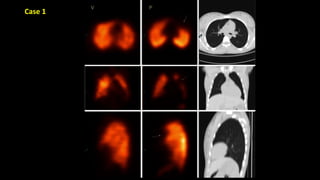

Case 1

Normal V/Q study

Ventilation [v] images on top row and perfusion [p] images beneath.

No defects are seen in either series.